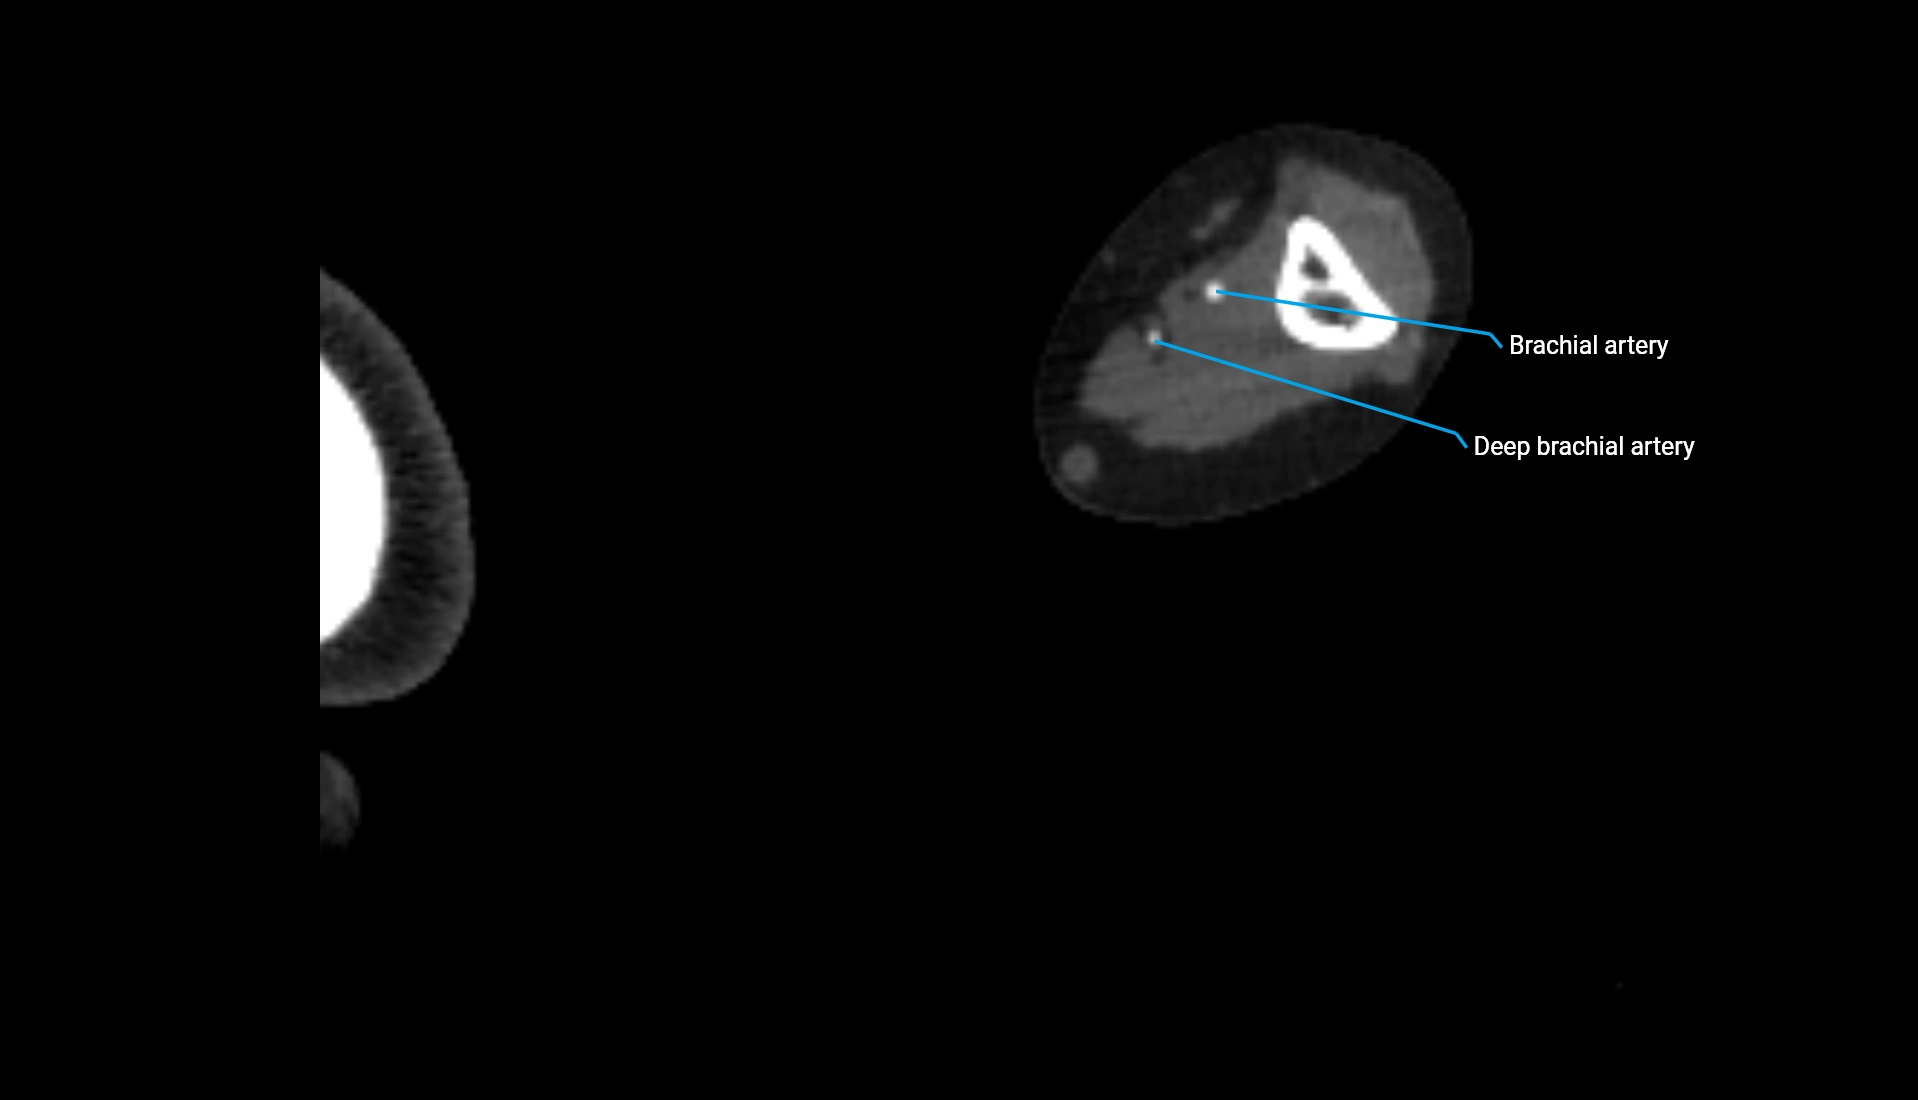

CT Appearance

Non-Contrast CT:

• Cortex: High-density, sharply defined

• Subchondral bone: Dense cancellous matrix

• Articular surface: Smooth concave contour articulating with the capitellum

• Excellent for evaluating bone integrity, alignment, and subtle fractures